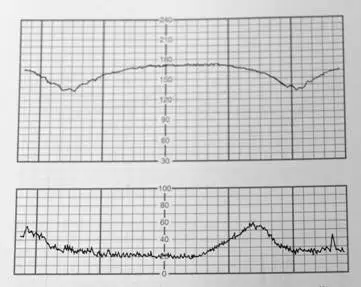

CTG 圖由上下兩個 panel 構成:

- 上 panel(FHR 曲線):基礎心率(baseline FHR)約 150 bpm,屬正常範圍(正常 110–160 bpm)。圖中可見兩個明顯的心搏減速(deceleration),波形平滑、緩慢下降並緩慢回升,形態對稱。

- 下 panel(宮縮曲線):顯示兩次子宮收縮,波峰清晰。

- 關鍵觀察:每次 FHR 的最低點(nadir)出現在宮縮波峰之後,即 deceleration 的起始、最低點、回復均落後於宮縮的起始、波峰、消退——這是 late deceleration 的定義特徵。

- 減速幅度較淺(約 15–20 bpm),波形緩慢、平滑,無急陡下降,排除 variable deceleration 的「V 形」急速下降型態。